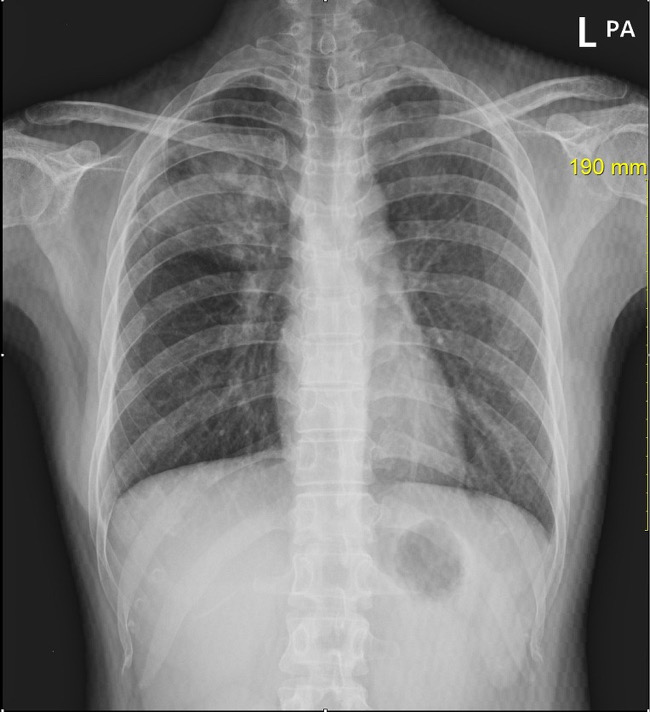

중국 장쑤성의 장쑤사범대 내에서 학생들이 무더기로 결핵에 감염되었는데 이들 학생들의 CT촬영에서 심각한 폐손상이 나타났다.